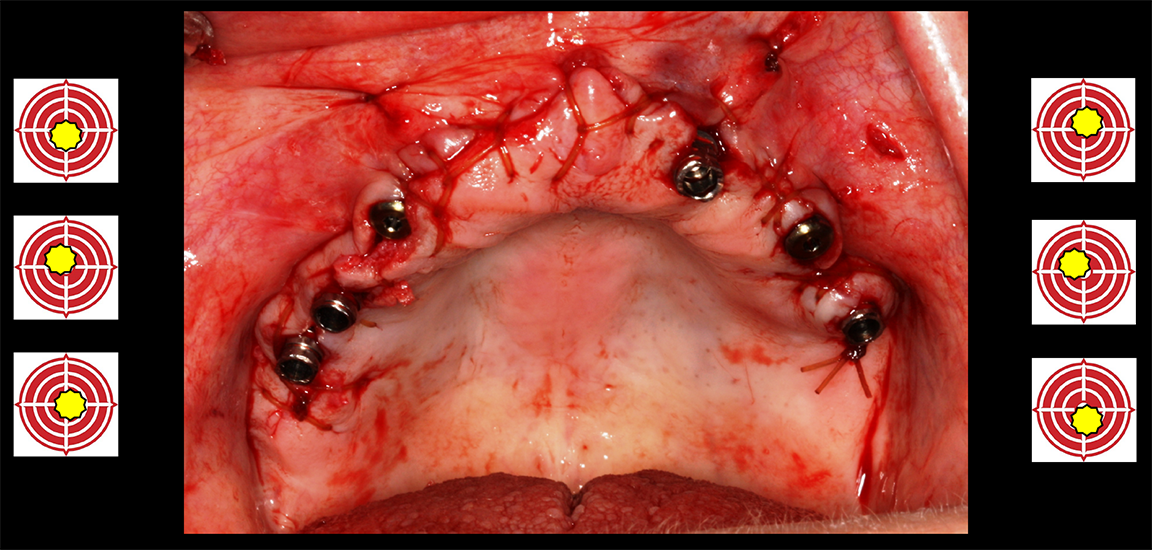

A patient tracker arm attaches directly to the patient's bony structure via surgical splint fitting deep down into the vestibular area. With threaded screws, it fixates more solidly than a surgical guide and is rigidly secured to the patient (Figure 12). This allows registration of the robot and the plan to the patient's anatomy and enables the handpiece of the robotic system to help the practitioner deliver the osteotomy and eventually the implant, unobstructed by multiple layers of printed plastic and unimpeded for irrigation, visual access, and bone reduction.2-4

Fig 12. A patient tracker arm attaches directly to the patient’s bony structure with a surgical splint.

Figure 12